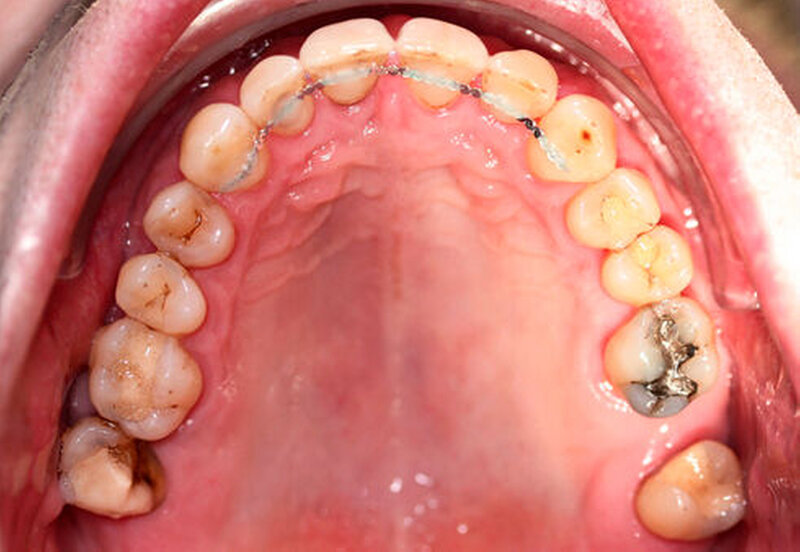

Anamnestisch lagen keine Besonderheiten vor. Es ist jedoch zu vermerken, dass ein regelmäßiger Alkohol-, Koffein- und Nikotinkonsum zugrunde lag. Intraoral zeigte sich ein bereits konservierend versorgtes permanentes Gebiss mit aktivem und inaktivem kariösen Geschehen. Große Anteile der Zahnhälse lagen nach Zahnfleischrückgang in Kombination mit Knocheneinbrüchen frei. Zahn 27 wurde bereits extrahiert.

Eine Beurteilung der parodontalen Situation an Zahn 11 offenbarte mesial und distal Sondierungstiefen von jeweils 6 mm.

Kieferorthopädisch imponierte beidseits eine neutrale Verzahnung bei einem tiefen Biss von 5 mm – bedingt durch die Verlängerung beider Frontzahngruppen. Besonders Zahn 11 zeigte eine erhebliche Verlängerung und Protrusion mit einer sagittalen Frontzahnstufe von 5 mm. Sowohl die Frontzähne im Ober- als auch im Unterkiefer wiesen eine lückige Beziehung zueinander auf (Abbildung 1).